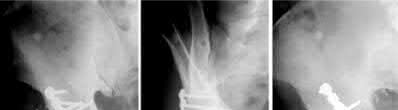

Question 10:

A hemodynamically unstable 42-year-old male is brought to the trauma bay after a motorcycle crash. Pelvic radiographs demonstrate an APC-III pelvic ring injury ('open book' pelvis). A pelvic binder is immediately applied by the trauma team. Which of the following statements regarding the application and function of a pelvic binder is most accurate?

To be effective in reducing pelvic volume and closing an open-book pelvic injury, a pelvic binder (or sheet) must be centered low, directly over the greater trochanters. Positioning it too high over the iliac crests can actually worsen the deformity by acting as a fulcrum. Its primary mechanism of action is reducing pelvic volume to encourage tamponade of the massive venous plexus bleeding, not arterial bleeding.